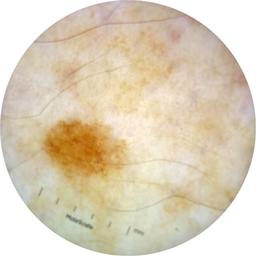

ISIC_9472333

Information

2057 x 2057

Clinical

Field Value

acquisition_day 230

age_approx 65

anatom_site_1 Trunk

anatom_site_2 Anterior trunk

anatom_site_general anterior torso

concomitant_biopsy False

diagnosis_1 Benign

diagnosis_confirm_type single image expert consensus

family_hx_mm True

fitzpatrick_skin_type I

image_manipulation instrument only

image_type dermoscopic

lesion_id IL_9967494

patient_id IP_4296977

personal_hx_mm True

sex female